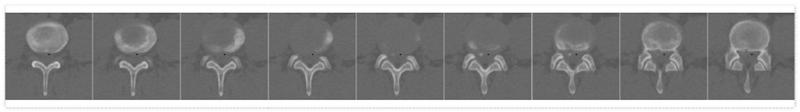

配准融合CT和MRI信号建立人体腰椎三维仿真模型的方法